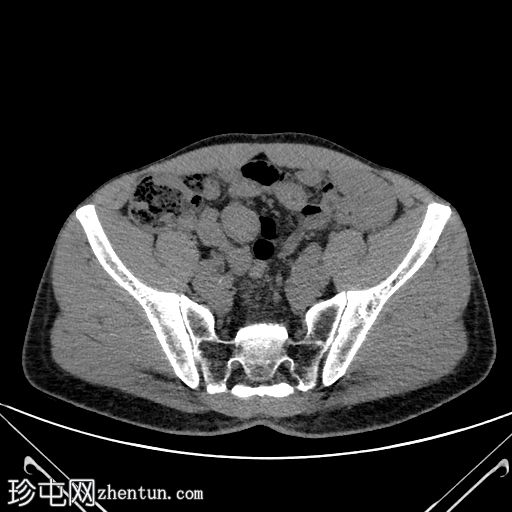

2.jpg

轴向C+期

动脉期

边界清晰,单发,均匀强化,实性,无坏死,盆腔内肠系膜肿块病变。

无可疑区域淋巴结肿大,无相关钙化,亦无其他强化间叶病变。

周围结构未见明确侵犯。

下腔静脉扩张至3.6 cm,意义不明。